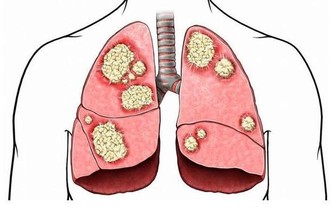

因而角膜會逐漸變尖,最終形成圓錐角膜,圓錐角膜的後果是使視力永遠喪失。

而一些醫院為了獲取暴利,沒有將這一後果告知患者.

醫院所說的激光手術不會致盲的觀點是錯誤的,而圓錐角膜就可以被認為是間接的致盲。

實行了LASIK後所產生的圓錐角膜目前在醫學上被認為是絕症,最後只能用角膜移植來解決問題!